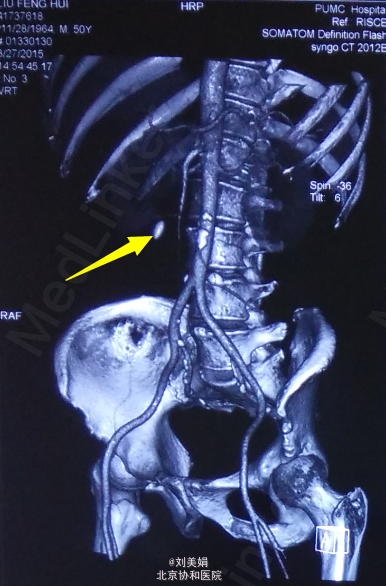

主 诉:体检发现右肾结石8个月 现病史:患者2014-11体检超声发现右肾结石,未予特殊诊治。2015-03因“类风湿性关节炎”入住我院普通内科,期间查泌尿系超声:右侧输尿管上段宽0.7cm,内见条状强回声,长约1.8cm,后伴声影,右侧输尿管中下段显示欠清。考虑右输尿管上段结石伴输尿管稍扩张,右肾盂分离。行CTU检查:右肾盂-输尿管连接处(UPJ)见类圆形密度增高影,大小约15mm×10mm,平扫CT值约1255Hu,其近端输尿管及右肾盂肾盏轻度扩张积水,壁略增厚毛糙,病灶周围见多发索条影。 小便夜尿增多,3-5次/晚,一年体重下降3kg。 右肾区轻度叩击痛,右输尿管走行区轻度压痛。

泌尿系结石双能量CT+成分分析:右输尿管-肾盂连接处(UPJ)见类圆形高密度影,大小约13mm×10mm,CT值约1049Hu,其近端输尿管及右肾盂肾盏扩张积水,输尿管及肾盂壁略增厚毛糙,病变周围多发索条影。左侧肾盂肾盏及输尿管未见明显异常。前列腺增大伴钙化灶。 泌尿系结石双能量成分分析:右UPJ结石主要成分为草酸盐。